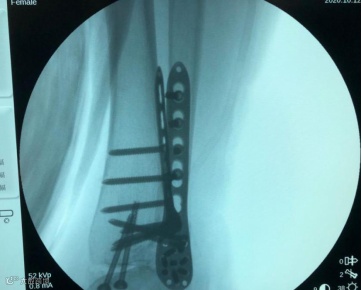

刘传见主任见状,立即带领全科医生为老奶奶制定了详细的手术治疗方案,决定启用自主研发的术中骨折电动牵引复位器!与传统机械牵引复位器相比,这种复位器具有全自动操作、完美适配手术床、全程无菌、牵引效果稳定等优点,且患肢可随时与牵引器解离,满足术中随时牵引和去牵引的需要。

在C型臂X线机的实时反馈和术中骨折电动牵引复位器的稳固牵引下,手术取得圆满成功!